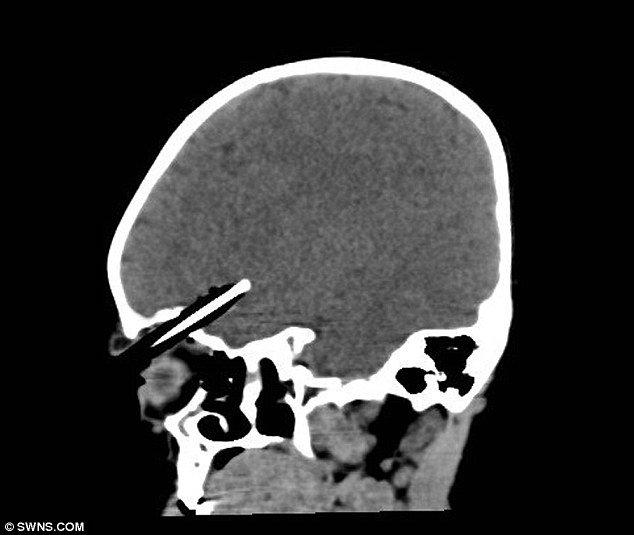

Οι ακτινογραφίες έδειξαν ότι το τραύμα ήταν πολύ σοβαρό και απαιτούνταν η παρέμβαση ενός ειδικού.

«Το μολύβι ήταν ένα χιλιοστό μακριά από το να χτυπήσει ένα μεγάλο αιμοφόρο αγγείο στον εγκέφαλο. Η μικρή ήταν πολύ τυχερή που γλίτωσε χωρίς μεγάλη αιμορραγία», ανέφερε ο νευροχειρουργός Ίαν Πόπλ.

Επίσης, σύμφωνα με τον Πόπλ το μολύβι δεν τραυμάτισε τον βολβό του ματιού.

Οι γιατροί έπρεπε να της αφαιρέσουν μέρος του κρανίου της για να μπορέσουν να κάνουν την επέμβαση.